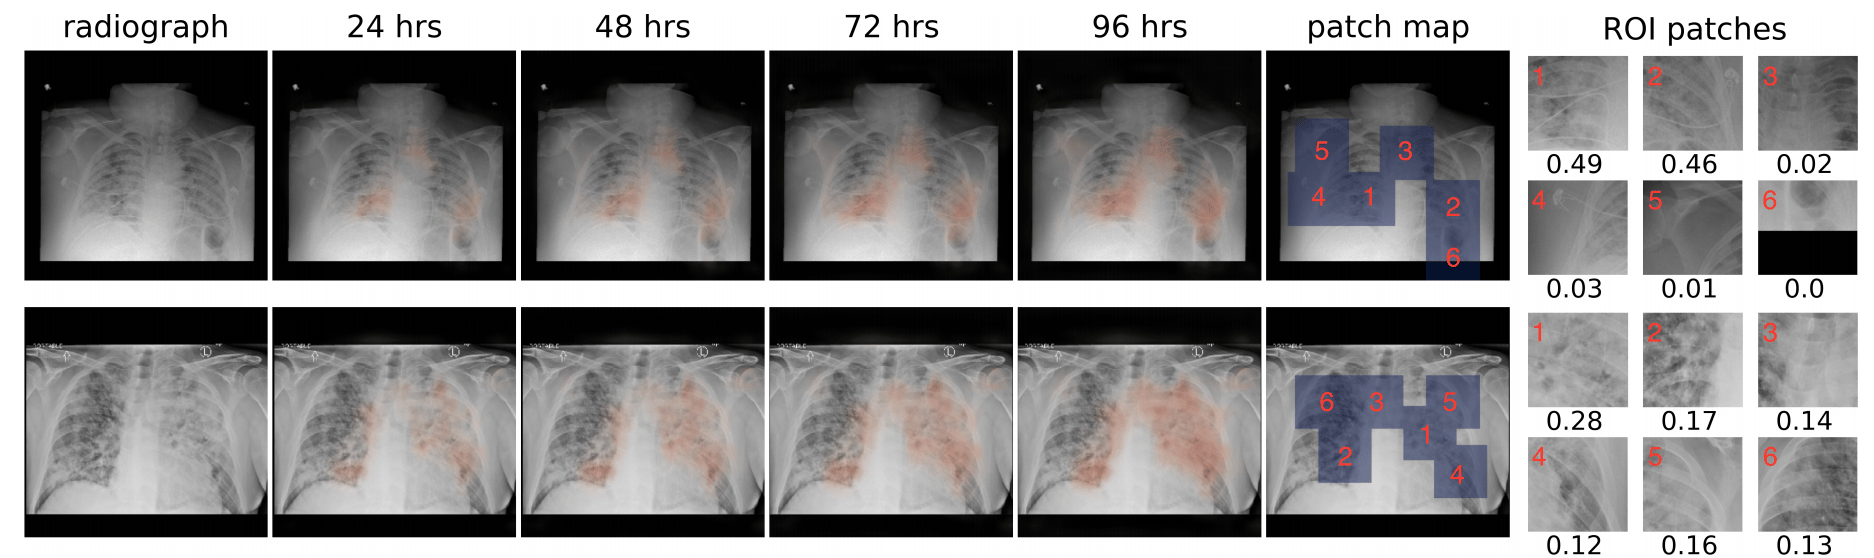

We processed the chest X-ray images using the Globally Aware Multiple Instance Classifier (GMIC) neural network architecture [1]. COVID-GMIC predicts the overall risk of deterioration within 24, 48, 72, and 96 hours, and computes saliency maps that highlight the regions of the image that most informed its predictions. As shown in Figure 2, COVID-GMIC utilizes the global network to generate four saliency maps that highlight the regions on the X-ray image that are predictive of the onset of adverse events within the four time windows. COVID-GMIC then applies a local network to extract fine-grained visual details from these regions. Finally, it employs a fusion module that aggregates information from both the global context and local details to make a holistic diagnosis. The predictions of COVID-GMIC are combined with predictions of a gradient boosting model [2] that learns from routinely collected clinical variables, referred to as COVID-GBM. The optimal weights assigned to the COVID-GMIC prediction in the COVID-GMIC and COVID-GBM ensemble were derived through optimizing the performance on the validation set (obtained from the folds of the Monte Carlo cross validation iterations).

Interpretability to establish trust with clinicians

We also qualitatively evaluated the saliency maps computed by COVID-GMIC. Two examples are shown in Figure 3. Both patients were admitted to the intensive care unit and were intubated within 48 hours. In the first example, there are diffuse airspace opacities, though the saliency maps primarily highlight the medial right basilar and peripheral left basilar opacities. Similarly, the two regions of interest (ROI) patches (1 and 2) on the basilar region demonstrate comparable attention values, 0.49 and 0.46 respectively. In the second example, the extensive left mid to upper-lung abnormality (ROI patch 1) is highlighted, which correlates with the most extensive area of parenchymal consolidation.

Figure 3: From left to right: the original X-ray image, saliency maps for clinical deterioration within 24, 48, 72, and 96 hours, locations of region-of-interest (ROI) patches, and ROI patches with their associated attention scores.